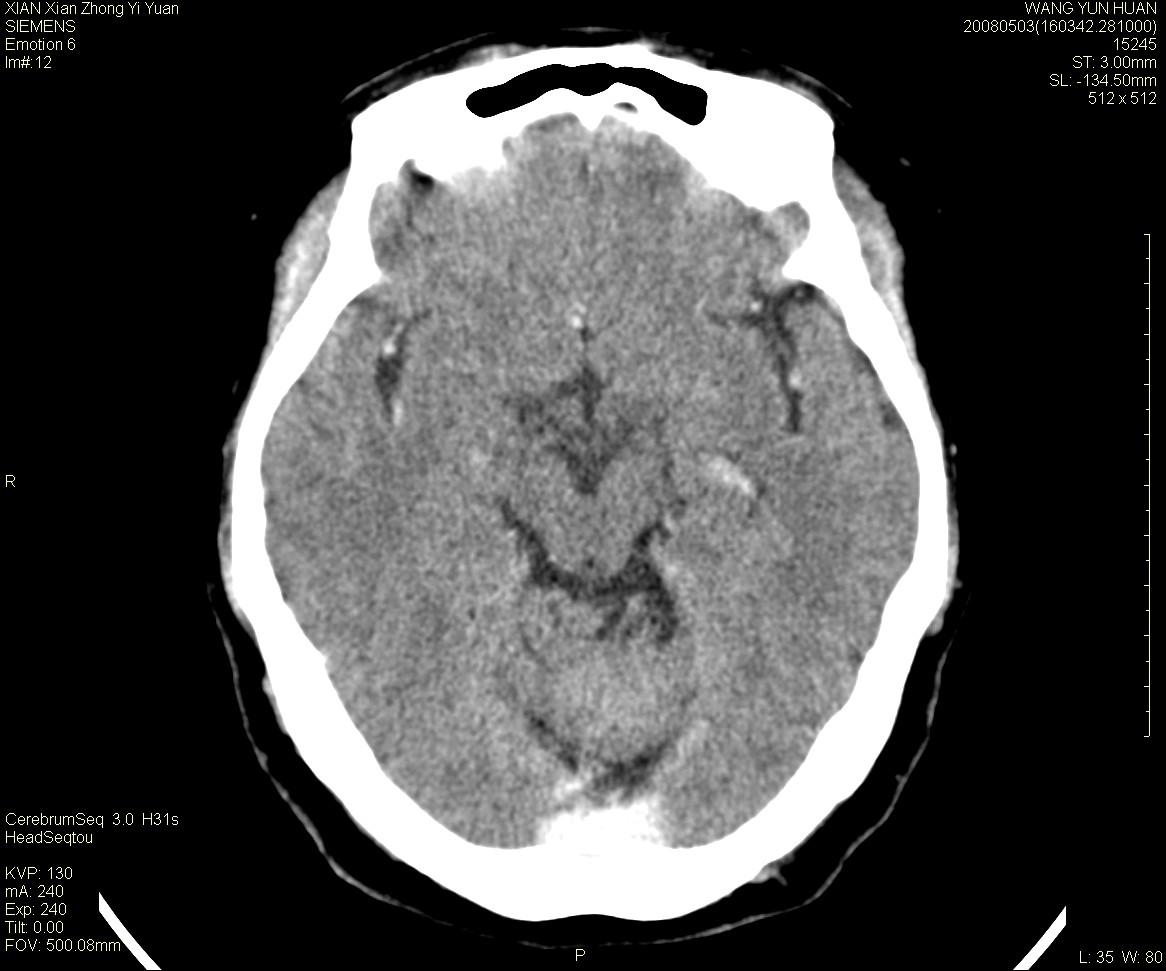

病灶显示轻度强化,ct增加4hu左右,大家看是什么肿瘤.

强化后动脉期及延迟2分钟,五分钟图像

小脑蚓部囊型肿块,内有实性结节及钙化点。增强后囊壁及结节轻度强化。

考虑蚓部星形细胞瘤(ⅱ级可能性大)。

小脑蚓部肿块,周围无明显占位效应及水肿带,增强轻度强化,考虑低分级星形细胞瘤。